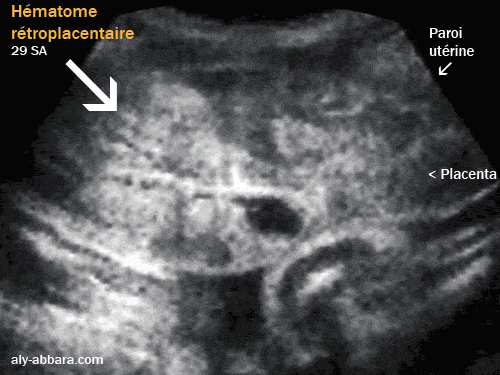

Décollement prématuré, massif et central d'un placenta normalement

inséré à 29 semaines d'aménorrhée

Image à comparer au décollement prématuré latéral du placenta

• Cette image échographique montre un important hématome rétroplacentaire décidual basal avec le décollement de plus de 90 % de la surface de l'insertion placentaire sur la paroi antérieure de cavité utérine.

• Seuls signes cliniques : douleurs pelviennes constantes et hypertonie utérine sans relachement, motivant la réalisation de l'échographie.

Pas de métrorragie, pas d'anomalie du rythme cardiaque fœtal. Tension artérielle oscillant entre 13,5 - 14,5 / 7,5 -8,5.

Biologiquement la protéinurie est à 300 mg/l ; hémoglobine à 12,1 g/l ; numération plaquettaire à 243 giga/l ; TP à 100 % ;TCA à 33 secondes/témoin 33 secondes ; fibrinogène à 3,8 g/l ; créatininémie à 51 µmol/l et uricémie à 342 µmol/l ; bilan hépatique normal.

• Césarienne en extrême urgence permettant la naissance d'un enfant vivant de 1220 g - indice d'Apgar 4/7/7 avec une évolution ultérieure rassurant.

Le placenta était décollé à 100 % à l'extraction ; il a été évacué un hématome de 500 - 600 cc de caillots sanguins. Une inertie utérine per-opératoire immédiate ne cédant pas à l'administration de l'oxytocine et nécessitant l'administration de Sulprostone en IVD (500µg/en une heure).

• Le bilan biochimique per-opératoire montre un taux d'hémoglobine à 10 g/l ; numération plaquettaire à 221 giga/l ; TP 74 % ; TCA à 37 secondes/témoin 33 secondes ; fibrinogène à 2 g/l ; PDF (produits de la dégradation de fibrinogène) à 320 µg/ml et complexe soluble négatif.

Le bilan réalisé 30 heures après la césarienne montre un taux d'hémoglobine à 8,7 g/l ; numération plaquettaire à 190 giga/l ; TP 93 % ; TCA à 42 secondes/témoin 33 secondes ; fibrinogène à 4,1 g/l ; PDF à 5

µg/ml.